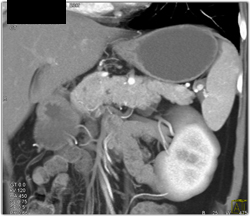

Encased PV/SMV By Tumor